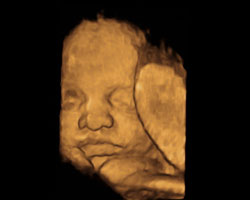

Se te estás a perguntar como será o teu bebé na barriga durante esta semana de gravidez, oferecemos-te aqui uma ideia aproximada. Mostramos-te uma ecografia e um vídeo muito interessantes, com o bebé em movimento. Incrível!

Idade do feto: 32 semanas